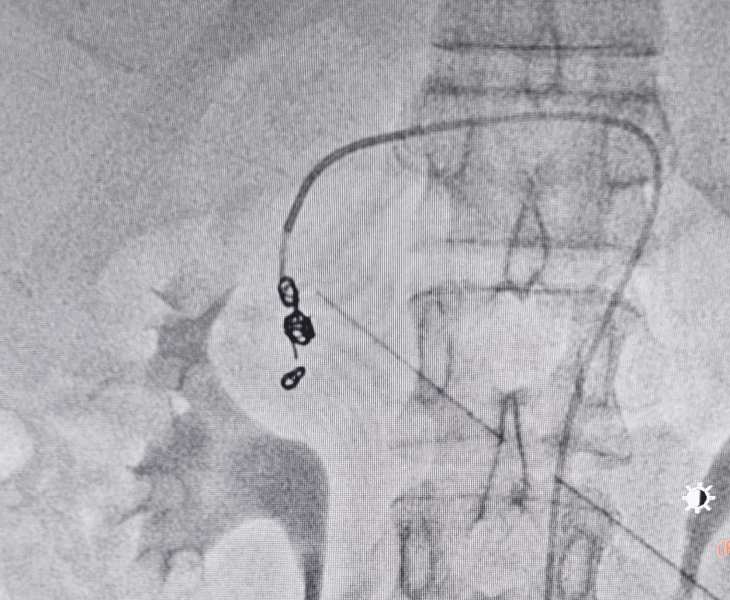

Embolization is performed in a catheterisation lab under fluoroscopy (X‑ray) guidance, usually through a tiny puncture in the groin or wrist artery.

- Catheter angiography: contrast is injected to locate the pseudoaneurysm and bleeding source.

- Super‑selective catheterisation: a microcatheter is advanced into the specific branch feeding the pseudoaneurysm.

- Embolization: coils and/or other embolic agents are deployed to stop blood flow to the pseudoaneurysm.

- Post‑embolization check: repeat angiography confirms complete sealing with preserved flow to normal tissues.